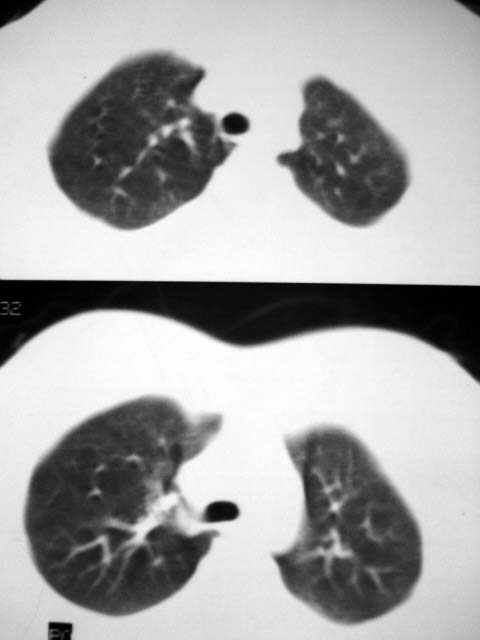

标题: CT12463:女,19岁,炎性假瘤?结核球? [打印本页]

女,19岁,体检时发现。炎性假瘤?结核球?

大家认为传片顺序是肺窗、纵隔窗分开传或是肺窗、纵隔交叉传,那一种更好呢?

请发表你的高见,是个人习惯或是专业方面有规定呢?

支持炎性改变。个人习惯不一,但纵隔窗与肺窗交叉看比较方便观察。